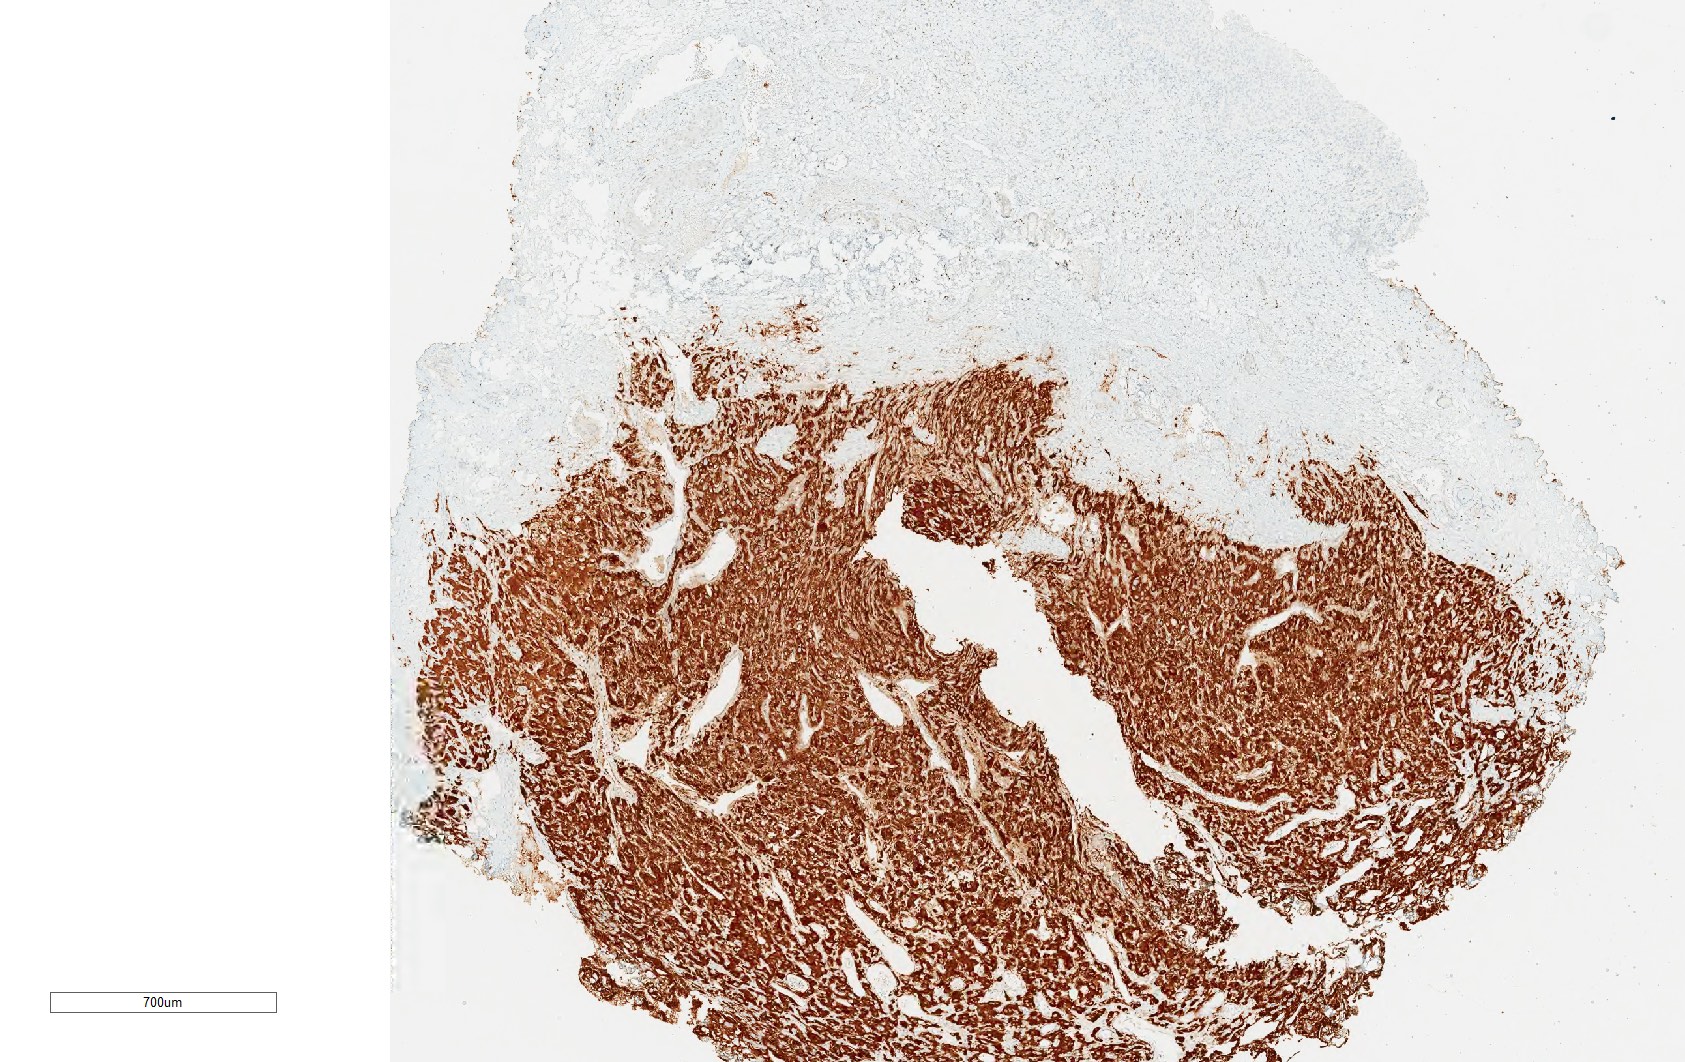

- Tumor cells are positive for GATA3 and neuroendocrine markers while negative for keratins; sustentacular cells are positive for S100 and SOX10

Contributed by Theodorus H. van der Kwast, M.D., Ph.D., Michelle R. Downes, M.D., Debra L. Zynger, M.D. and David Cohen, M.B.B.Ch., M.D.

Positive stains

- INSM1 (diffuse), chromogranin A (variable, often diffuse), synaptophysin (variable, usually diffuse) (Endocr Pathol 2022;33:90)

- GATA3

- Sustentacular cells: S100, SOX10

- Microscopic description: This specimen shows an unencapsulated, monomorphous population of round tumor cells in a nested / zellballen pattern with delicate vascular septa and intervening extravasated red blood cells. It predominantly involves the lamina propria of the bladder but in 1 tissue piece clearly involves muscularis propria. The tumor cells have abundant amphophilic cytoplasm and vesicular chromatin with occasional small nucleoli. There is no necrosis, diffuse growth pattern or vascular space invasion identified. The mitotic count is (maximally) 1/10 high power fields. Immunohistochemistry shows the tumor cells to be positive for GATA3 with strong and diffuse expression of synaptophysin and chromogranin, as well as retention of SDHB staining. The tumor cells are negative for AE1 / AE3, HMWK and p63. The Ki67 proliferation index is < 1%. S100 shows faint nuclear and cytoplasmic staining with occasional sustentacular cells identified.

- Microscopic description: Sections show unremarkable surface urothelium with a lesion in the deep lamina propria comprised of large eosinophilic cells with hyperchromatic, focally enlarged nuclei with occasional intranuclear inclusions. A fine vascular plexus is identified in some areas. Necrosis and hemorrhage are not identified. Mitotic rate = 1/10 high power fields (field of view [FOV] = 0.55 mm). The lesion extends to the cauterized base of the specimen. Immunostains confirm the lesion expresses synaptophysin, chromogranin and GATA3. SDHB is retained. AE1 / AE3, CD45, p63 and NKX3.1 are negative.